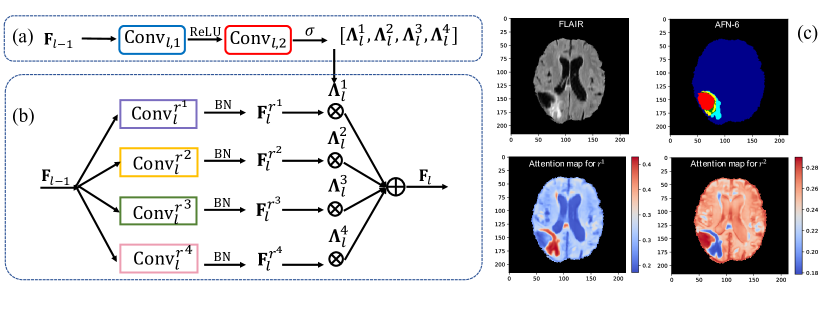

We propose the autofocus layer, a novel module that enhances the multi-scale processing of CNNs by learning to select the ‘appropriate’ scale for identifying different objects in an image. Our work on autofocus shares similarities with Aspp in that we also use parallel dilated convolutional filters to capture both local and more global context. The crucial difference is that instead of naively aggregating features from all scales, the autofocus layer adaptively chooses the optimal scale to focus on in a data-driven, learned manner. In particular, our autofocus module uses an attention mechanism [1] to indicate the importance of each scale when processing different locations of an image (Fig. 1). The computed attention maps, one per scale, serve as filters for the patterns extracted at that scale. Autofocus also enhances interpretability of a network as the attention maps reveal how it locally ‘zooms in or out’ to segment different context. Compared to the use of attention in [4], our solution is modular and independent of architecture.

Unambiguously classifying different objects in an image is likely to require different combinations of local and global information. For example, large structures may be better segmented by processing a large receptive field at the expense of fine details, while small objects may require focusing on high resolution local information. Consequently, architectures that statically define multi-scale processing may be suboptimal. Our adaptive solution, the autofocus module, is summarized in Fig. 1 and formalized in the following.

Given activations of the previous layer , we capture multi-scale information by processing it in parallel via convolutional layers with different dilation rates . They produce tensors (Fig. 1(b)), each set to have same number of channels . They detect patterns at different scales which we merge in a data-driven manner by introducing a soft attention mechanism [1].

Within the module we construct a small attention network (Fig. 1(a)) that processes . In this work it consists of two convolutional layers. The first, , applies 333 kernels, produces half the number of channels than those in (empirically chosen) and is followed by a ReLU activation function . The second, , applies 111 filters and produces a tensor with channels, one per scale. It is followed by an element-wise softmax that normalizes the activations for each voxel to add up to one. Let this normalized output be . Formally:

In the above, is an attention map that corresponds to the -th scale. For any specific spatial location (voxel), the corresponding values from the attention maps can be interpreted as how much focus to put on each scale. Thus the final output of the autofocus layer is computed by fusing the outputs from the parallel dillated convolutions as follows:

where is an element-wise multiplication. Note that the attention weights are shared across all channels of tensor for scale . Since the attention maps are predicted by a fully convolutional network, different attention is predicted for each voxel, driven by the image context for the optimal choice of scale (Fig. 1(c)).